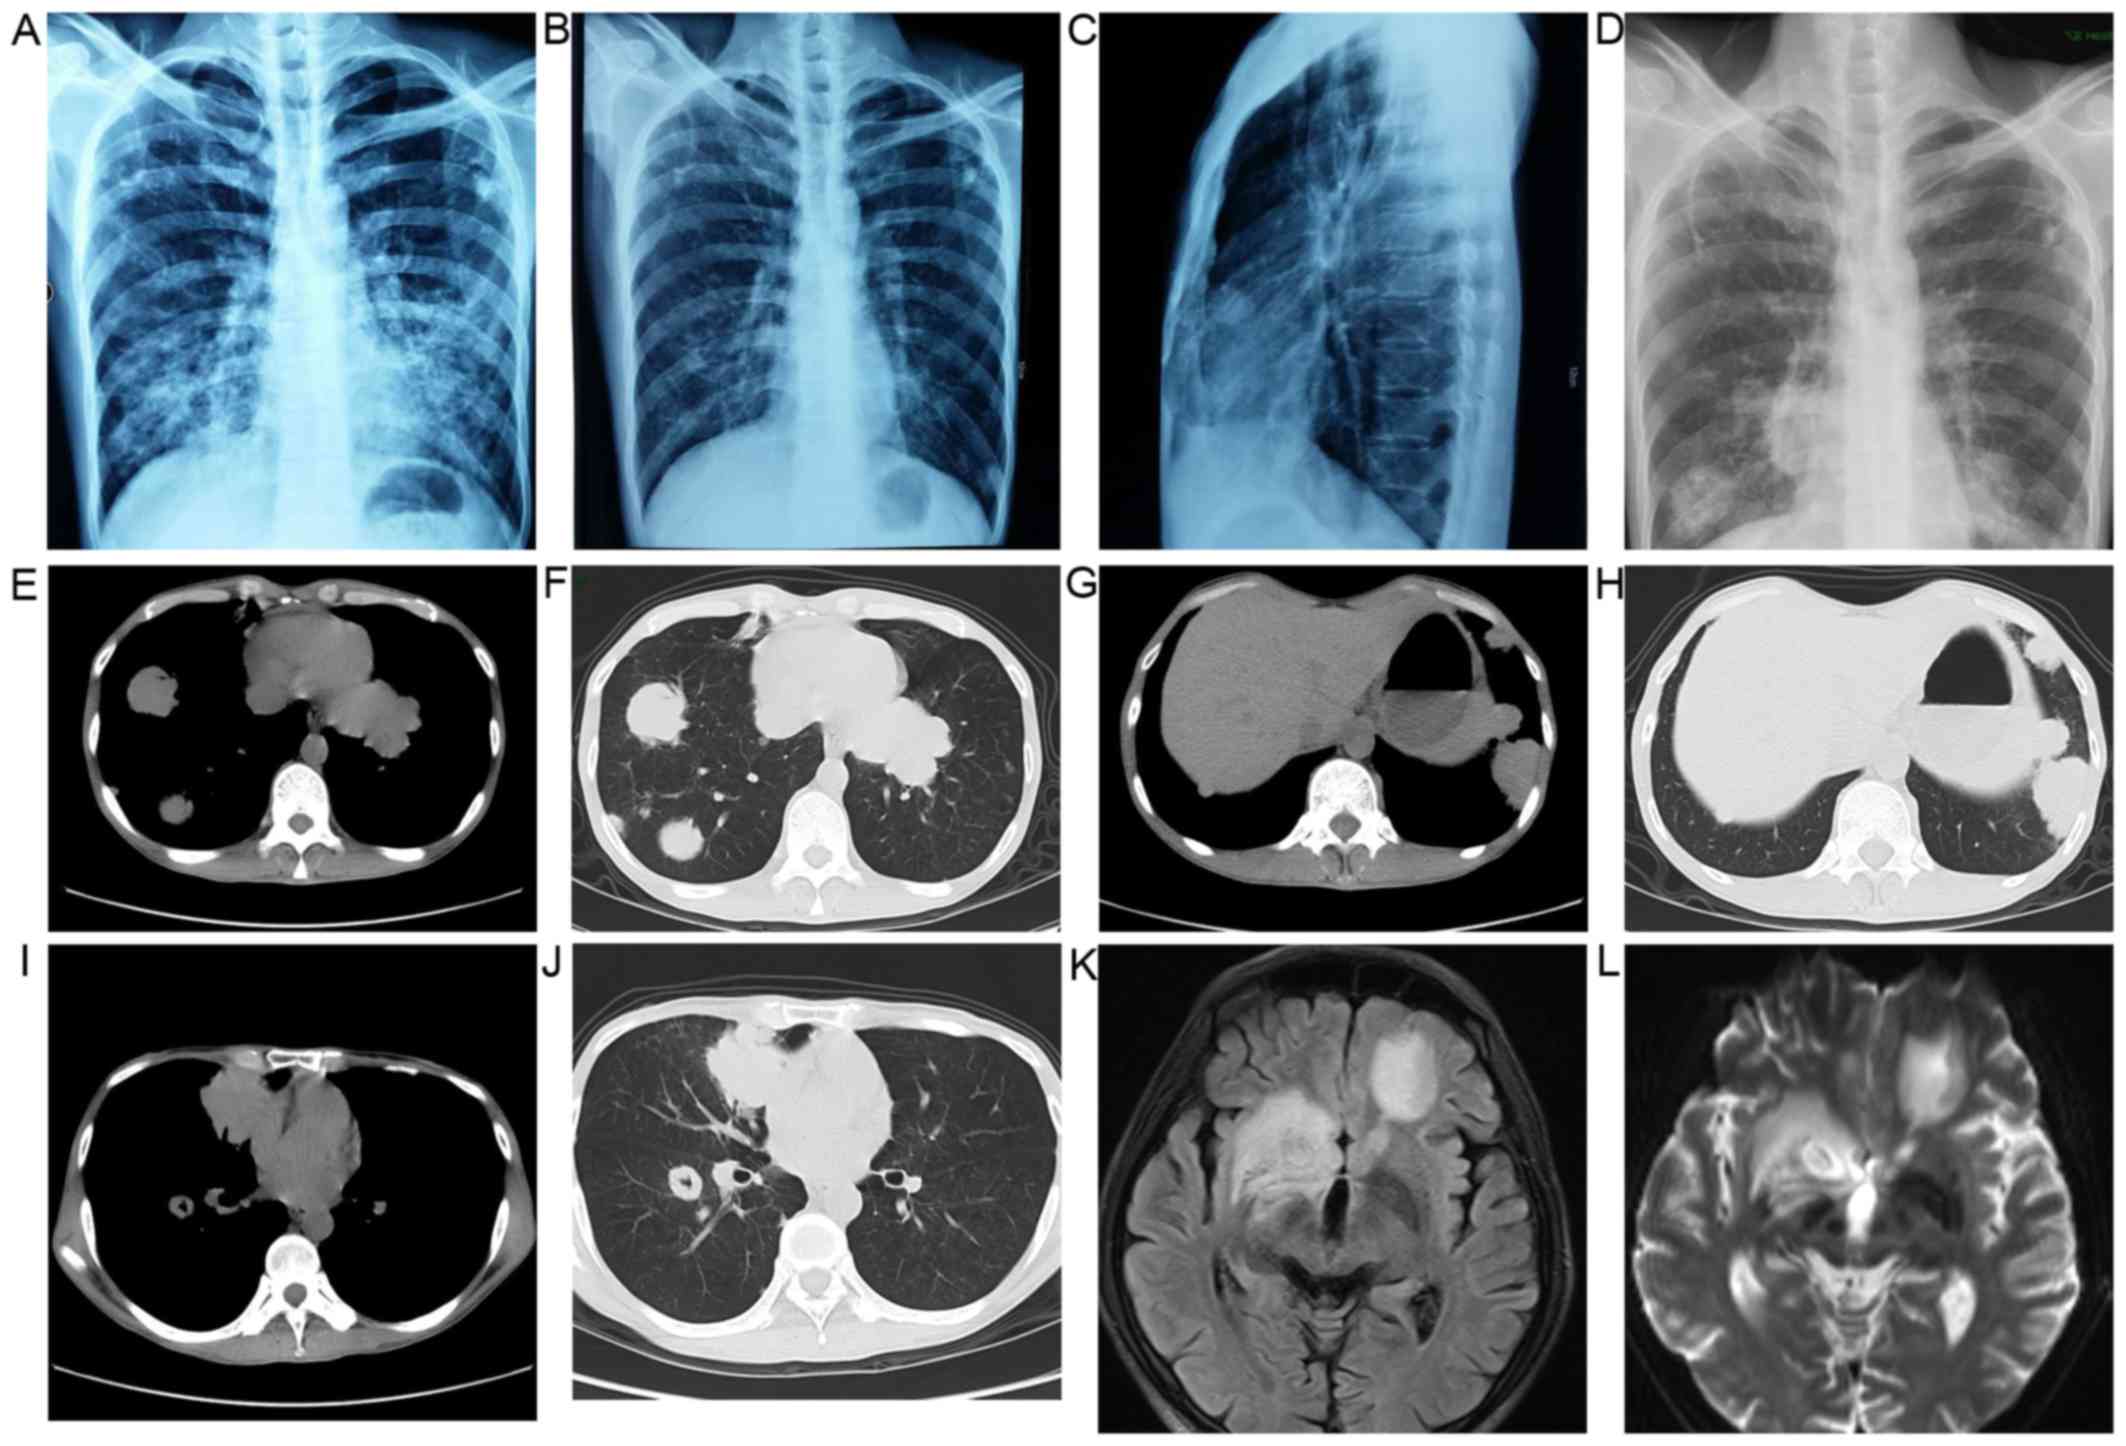

A 42-year-old man presented with a 2-week history of dry cough and thoracalgia accompanied by intermittent mild fever and headaches; however, no night sweats or weight loss were reported. The patient had a history of sexual contact with men. A total of 18 months prior to the presentation, the patient was diagnosed with pulmonary tuberculosis (TB) in a specialized hospital in China following the development of fever and cough. The results of acid-fast staining on sputum smear analysis and a chest X-ray showing infiltrates in both lungs were consistent with typical TB manifestations (Fig. 1A). Simultaneously, the patient was diagnosed with human immunodeficiency virus (HIV) infection. According to the guideline for adult HIV/AIDS patients with opportunistic infections recommended by the Center for Disease Control and Prevention, Infectious Diseases Society of America and National Institutes of Health (http://aidsinfo.nih.gov/guidelines), the specialist consultant at the TB specialized hospital empirically prescribed first-line anti-TB treatment for this patient with 2 months of isoniazid, rifampicin, ethambutol and pyrazinamide, followed by 4 months of isoniazid and rifampicin. As a result, the fever and cough were eliminated, and the pulmonary infiltrate was also absorbed (Fig. 1B and C). Thus, according to the guideline, further testing for anti-TB drug sensitivity was not deemed necessary. One month after the aforementioned treatments, lamivudine, tenofovir and efavirenz were administered to the patient as an additional anti-HIV treatment strategy; however, the medication was not taken regularly and follow-up appointments were also irregular. A physical examination was performed following admittance to the hospital, which revealed bilateral oral leukoplakia and tenderness in the left lower chest. Sputum acid-fast staining analysis did not reveal any signs of TB infection, and no anaerobic bacteria, aerobic bacteria, fungi or Mycobacterium tuberculosis were present in blood culture. The results of the laboratory tests performed on admission are presented in Table I. Lumbar puncture was performed due to the patient suffering from headaches; however, no pathogens were found in the cerebrospinal fluid (CSF). The results of CSF examinations are presented in Table I. A chest X-ray revealed multiple masses in both lungs (Fig. 1D) and a subsequent thoracic computerized tomography (CT) scan confirmed this result (Fig. 1E-J). Brain magnetic resonance imaging (MRI) revealed nodules in the left frontal cortex and the bilateral basal ganglia. (Fig. 1K and L). The patient was initially suspected to be suffering from a pulmonary and CNS infection; however, the X-ray and laboratory findings did not support this suspected diagnosis. To determine the composition of the lung and brain masses, a percutaneous lung needle biopsy was performed, revealing large numbers of lymphocytes ranging in size from medium to large, with oval or round nuclei containing fine chromatin and scanty cytoplasm (Fig. 2A-C). Furthermore, immunohistochemistry staining analysis revealed that these results were consistent with a diagnosis of germinal center B-cell-like (GCB) DLBCL (Fig. 2D-G). 18F-labelled fluorodeoxyglucose (FDG) positron emission tomography (PET) revealed that FDG uptake was high in the brain, mediastinum, lungs, right adrenal gland, thoracic vertebrae and ribs (Fig. 3). Based on these results, experienced radiologists suggested a diagnosis of systemic lymphoma with CNS involvement. Then, bone marrow aspiration was performed, and cytological examination revealed normal bone marrow hyperplasia, without the presence of lymphosarcoma cells. Therefore, the patient was diagnosed with stage IV NHL according to the Ann Arbor staging system for lymphoma (9), B group as he displayed one of the systemic B symptoms, including fevers (>38.5°C), drenching night sweats and/or weight loss (>10% of body weight over 6 months prior to diagnosis). The patient had a poor prognosis due to his high-intermediate risk (score 3) according to international prognostic index: Stage IV, high serum lactate dehydrogenase level, >1 extranodal sites (10) and CD4 cell count <100 cells/µl (11). Unfortunately, the patient refused chemotherapy or radiotherapy for the treatment of lymphoma due to his poor economic status and poor prognosis, and discharged himself from the hospital.

Figure 3.

FDG-PET scans revealed numerous high signal tumors. (A-F) PET scan images revealed that FDG uptake was high in the brain, mediastinum, lungs, right adrenal gland, thoracic vertebrae and ribs. FDG, fluorodeoxyglucose; PET, positron emission tomography.

PCNSL is a rare type of extranodal NHL (19), and congenital or acquired immunodeficiency is the only risk factor for this tumor that has been established to date. Patients with PCNSL have lymphosarcoma cells present in the CNS, which may induce lymphoma relapse (20). Unlike peripheral tumors, cerebral lymphoma is difficult to diagnose by histopathology. Therefore, MRI and PET-CT examinations can assist in the diagnosis of most CNS lymphomas. The typical findings of PCNSL on MRI are considered to be single lesions (60-70% of the cases) or multiple lesions (30-40% of the cases) without necrosis and with a relatively small oedema, which are usually localized in the periventricular space (21). FDG-PET has been shown to provide high accuracy in the differentiation between cerebral lymphomas and infectious lesions in patients with AIDS. Malignant processes tend to exhibit higher uptake compared with infections (22). In the present case, the brain MRI revealed nodules in the left frontal cortex and bilateral basal ganglia, and the FDG-PET revealed high signal in the brain, which were considered to be consistent with the MRI and PET characteristics of CNS lymphoma by experienced radiologists based on the NCCN Clinical Practice Guideline in Oncology (www.NCCN.org). Furthermore, other CNS malignancies were excluded, as the simultaneous presence of a systemic lymphoma and another carcinoma in the same patient is extremely rare. The most common pathogenic infections in the brain parenchyma of HIV/AIDS patients are toxoplasma, TB and cryptococcosis. The clinical presentation and laboratory tests for the presence of pathogenic microorganisms in the blood and CSF did not confirm the diagnosis of cerebral parenchymal pathogen infection in the present case. Furthermore, the radiographic appearance of the CNS lesions did not support this diagnosis. Therefore, infectious lesions of the brain were not considered in this case.